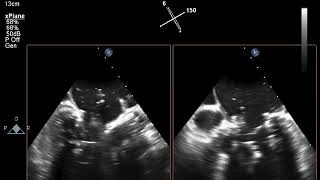

Video 3

Mitral stenosis pre-transcatheter mitral valve replacement.

Video 4

Mitral valve post-transcatheter mitral valve replacement.